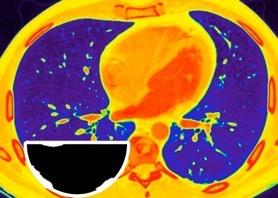

Hemorrágica………….30-70 UH

Extravasación iv. con sangrado activo……….>90 UH

“Simpático”………….,,,,<15 UH

Durso AM et al. Penetrating Thoracic Injury. Radiol Clin N Am 2015.

Urogénico……………….< 15 UH

Entérico.. ………………+/- 15UH

Biliar, Quiloso……………..<0 UH

Abramowitz1 Y et al. Pleural Effusion: Characterization with CT Attenuation Values and CT Appearance .AJR 2008